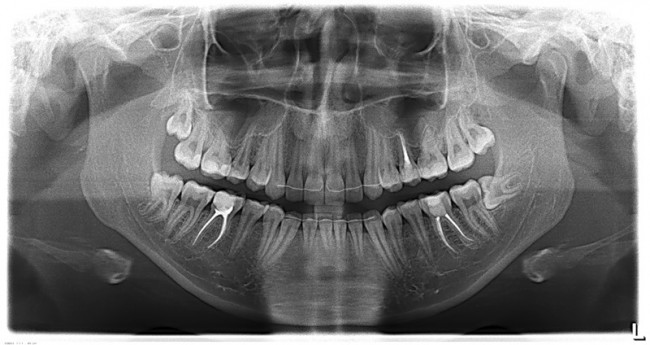

Далее, приступаем к удалению. Неплохо было бы ознакомиться со снимками, для начала — ведь большая часть зуба находится, как известно, вне нашего зрения и видна только на рентгенограммах.

Пара слов о рентгеновских снимках. Нередко слышу два умозаключения:

«на ортопантомограмме корни верхних зубов

находятся в проекции альвеолярной бухты верхнечелюстной пазухи,

поэтому обязательно будет перфорация и ороантральное соустье,

свищ, гайморит, ад и погибель.:»

«на ортопантомограмме корень нижнего зуба мудрости находится близко

(или пересекает) нижнечелюстной канал,

поэтому удаление зуба мудрости приведет к повреждению нижнелуночкового нерва

и последующему онемению половины челюсти, губы и подбородка:»

Разберем подробнее:

Во-первых, панорамный снимок — штука, сильно искажающая пространственное соотношение тканей и структур. Возьмите два листа бумаги с текстом с обеих сторон, сложите их вместе и посмотрите на просвет. Удается ли прочитать текст? Вот ортопантомограмма — примерно, то же самое. Другими словами, сказать по ортопантомограмме о соотношении верхнечелюстной пазухи и корней верхних зубов, равно как и о положении корней восьмерок и нижнечелюстного канала ДОСТОВЕРНО НЕЛЬЗЯ! Поэтому, для такой точной работы как дентальная имплантация, нам нужна компьютерная томография.

Во-вторых, можно просто посмотреть компьютерную томографию, либо сходить в анатомический театр, препарировать труп и убедиться, что корни верхних зубов, чаще всего, не попадают в верхнечелюстную пазуху, а обходят ее по сторонам. А, если и попадают, то между ними и пазухой остается слой костной ткани, надкостницы и слизистой оболочки гайморовой пазухи, которые, при правильной методике удаления, не дадут образоваться соустью. Редкое, очень редкое исключение из этого правила — длительный периапикальный процесс, который приводит к разрушению костной перегородки между лункой зуба и дном верхнечелюстной пазухи.

То же самое касается и нижнечелюстного нерва и восьмерок. Сделав компьютерную томографию мы убедимся, что нижнечелюстной нерв находится гораздо более язычно, нежели корень зуба. А на снимке они, нередко накладываются друг на друга создавая иллюзию пересечения.